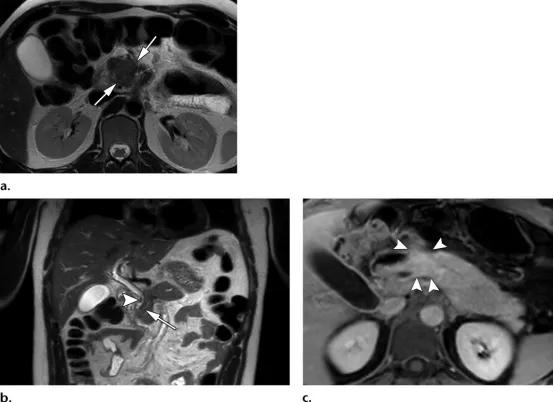

42岁男性,2型自身免疫性胰腺炎

(a图)轴位T2WI示胰腺近端边界不清的等信号肿块样病变(白色长箭头)

(b图)冠状位T2WI示胰管管径变窄,并横穿同一区域(白色长箭头),注意观察胆总管远端的局灶性狭窄(白色短箭头)

(c图)轴位增强延迟期磁共振示同一区域的局灶性肿物样病变(白色短箭头),其余胰腺未见明确异常。

35岁女性,1型自身免疫性胰腺炎,(a图)轴位T2WI示低信号纤维化边缘(白色长箭头),(b图)轴位增强磁共振示均匀强化的胰腺以及不强化的纤维边缘(白色长箭头)。